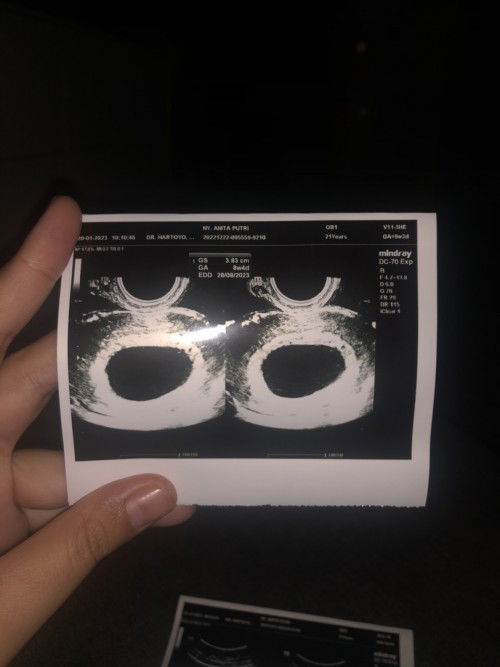

Usia kehamilan 8minggu 5hari tidak terlihat bakal janin

Mom, di usia kehamilanku yg 8minggu 5hari tapi pas di usg trans V bakal janin belum terlihat cuma kantongnya aja, tapi saya masih merasakan tanda tanda kehamilan seperti mual muntah di pagi hari dan tidak ada flek. Barangkali disni ada mom yg pernah mempunyai pengalaman yg sama seperti saya, bantu komen ya mom dan gimana kelanjutannya? Mudah mudahan dan insyallah #ingintahu #firstmom #pleasehelp #8minggu5hari janin saya sudah terlihat dalam 2minggu kedepan amin yarabb